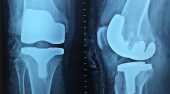

膝蓋